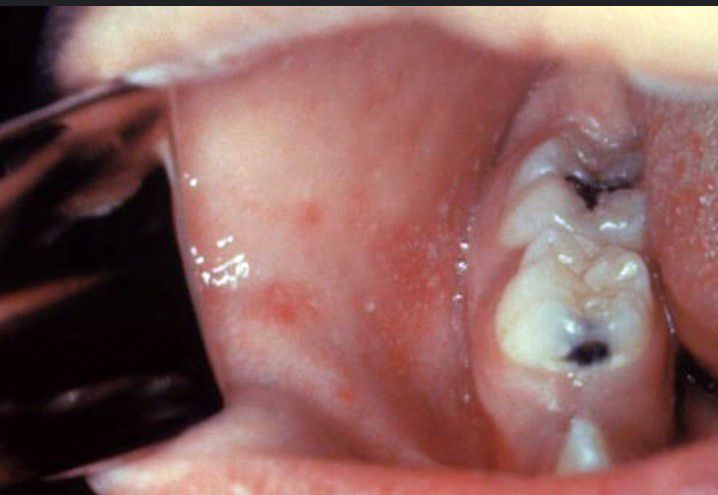

Koplik spots

Koplik spots are the peculiar spots present on the buccal mucosa and are considered a diagnostic/pathognomic feature of measles/rubeola in the pre-eruptive stage.